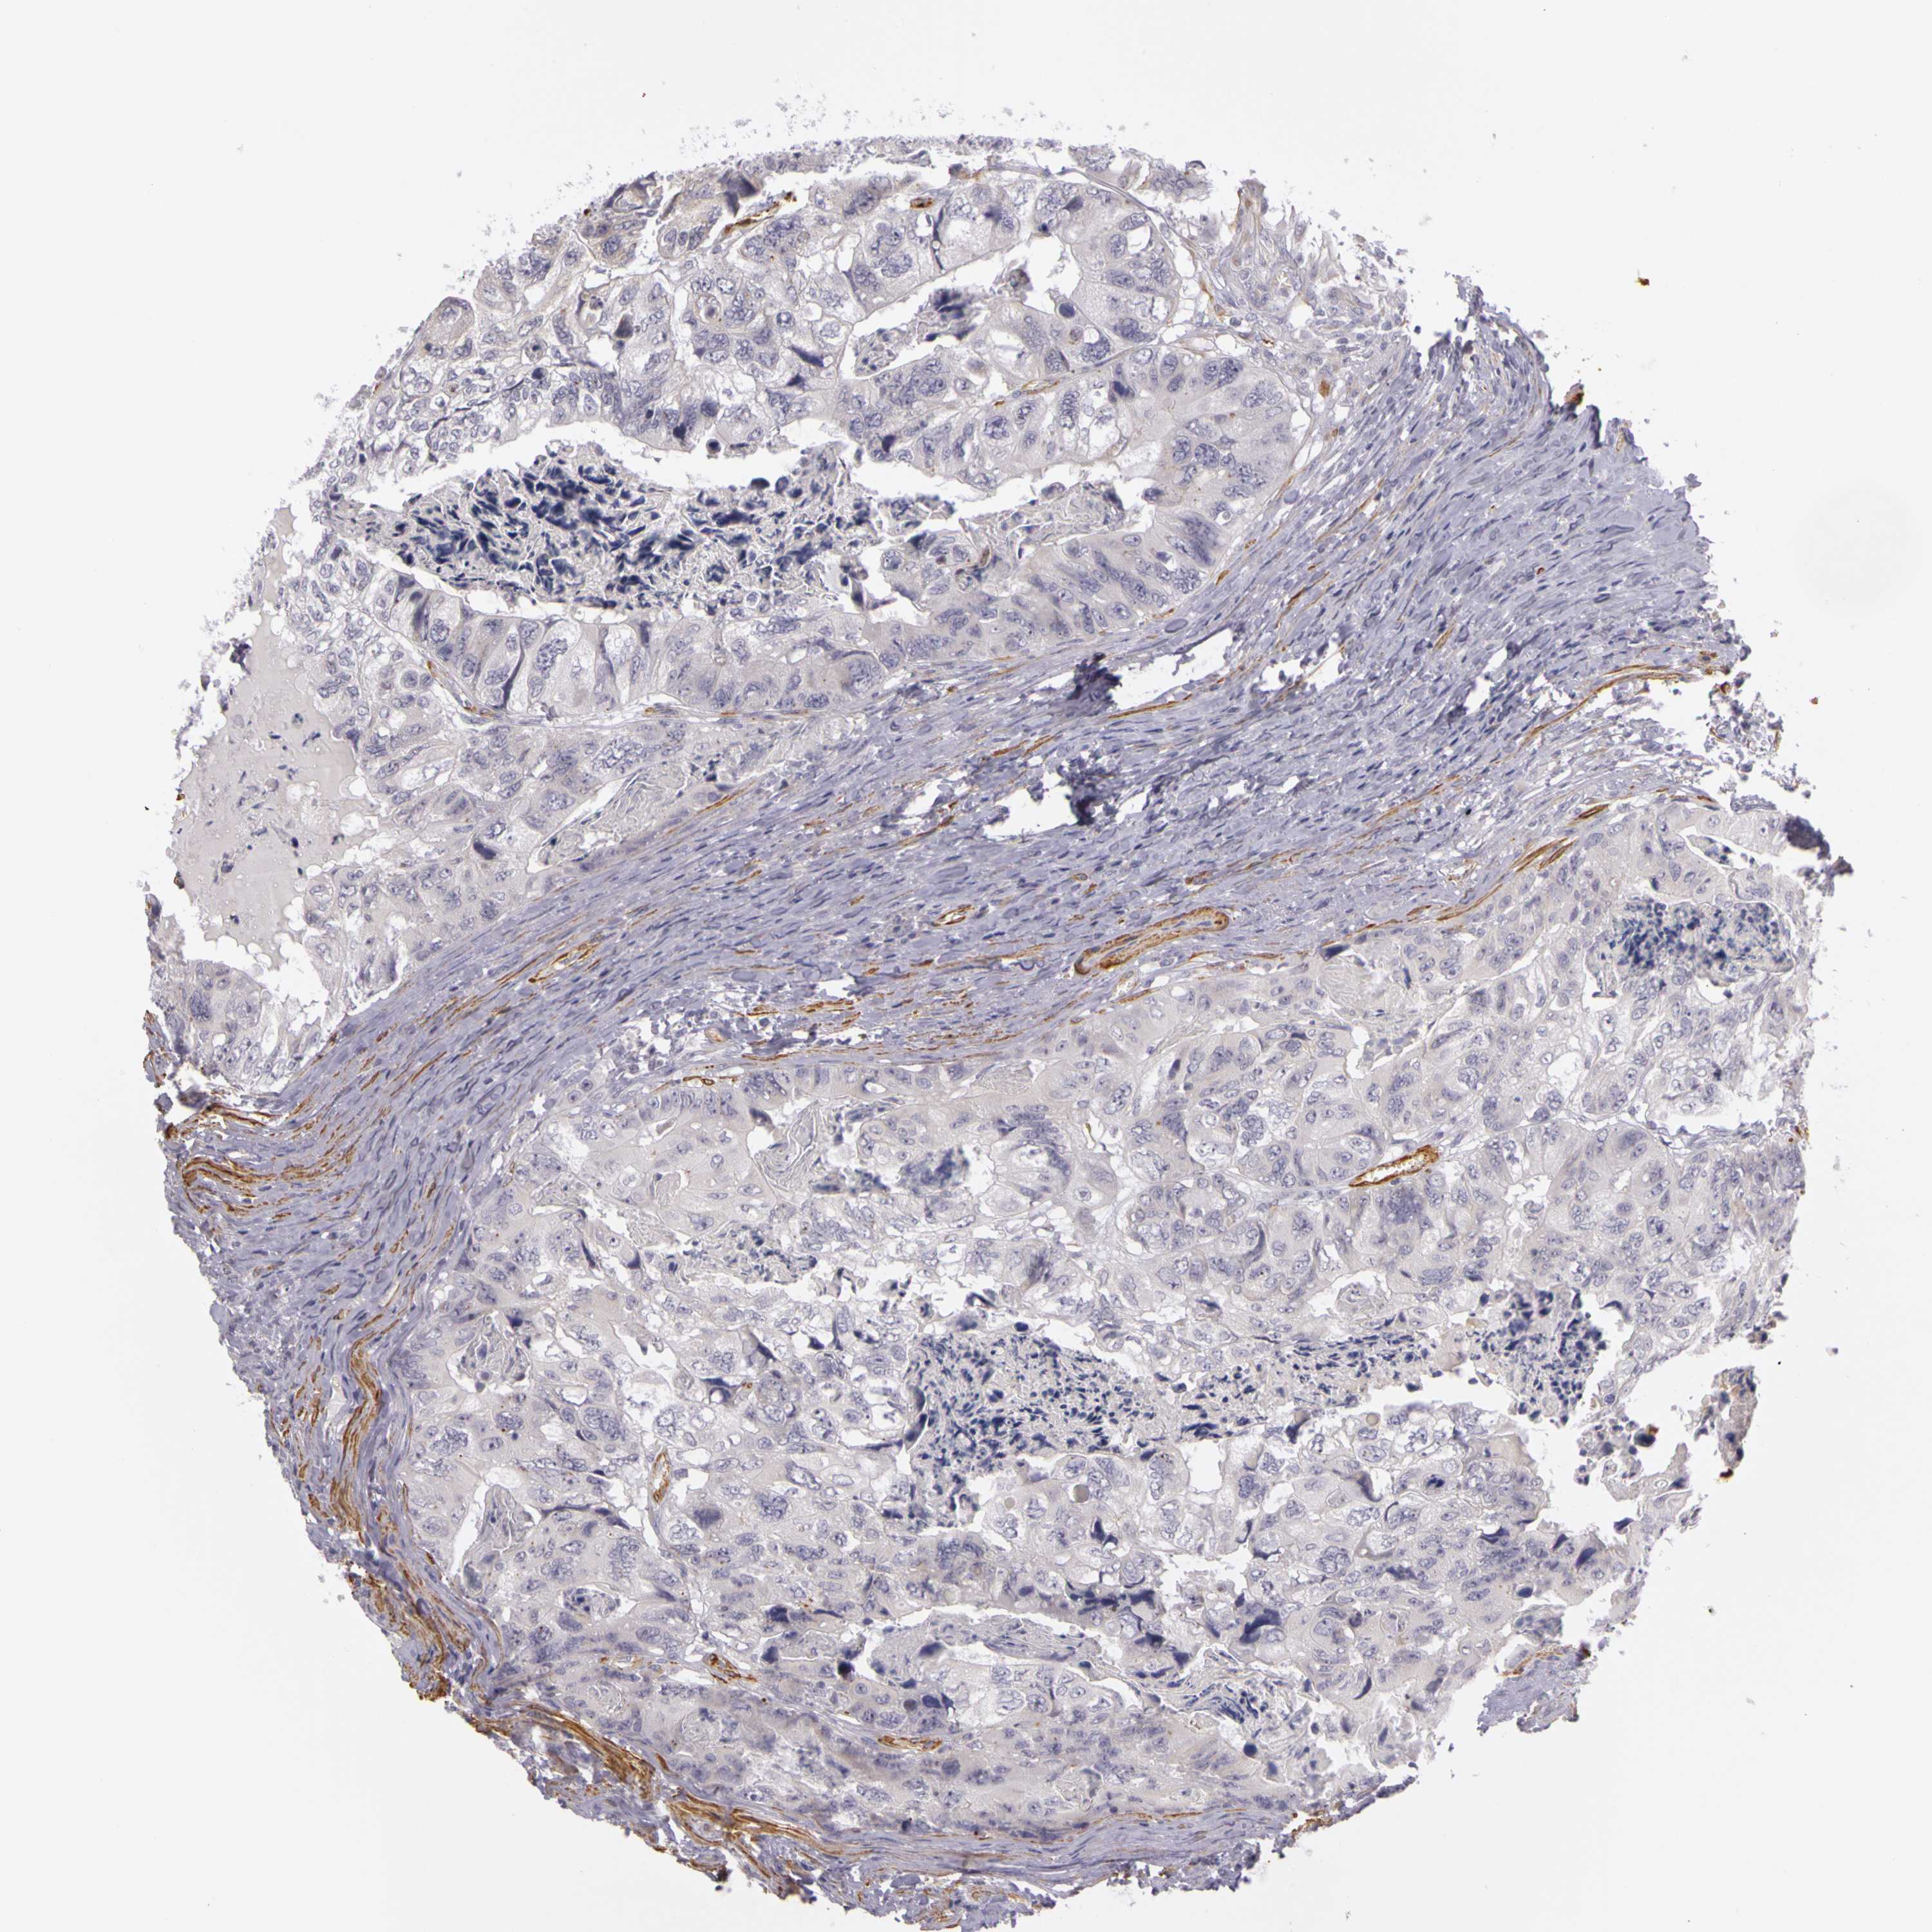

CANCER COLORECTAL CANCER Show tissue menu

Colorectal cancer

Colon adenocarcinoma